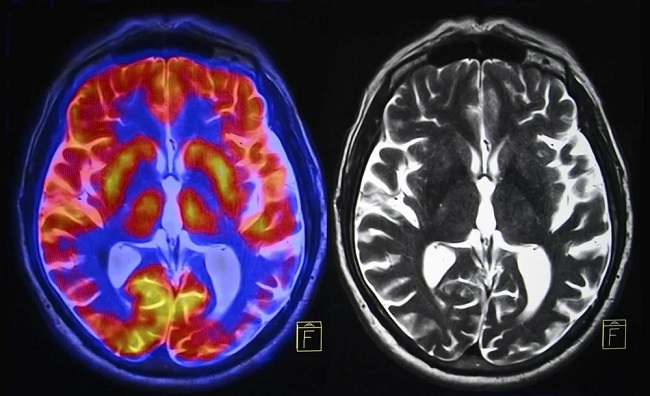

According to the case details, the patient first experienced moderate COVID-19 symptoms such as fever, cough, and chest tightness. Two weeks later, he began showing alarming neurological changes including confusion, difficulty concentrating, vertigo, and tremors. MRI scans showed extensive brain abnormalities, particularly in areas associated with cognition and motor control. His cerebrospinal fluid (CSF) tests later confirmed high concentrations of proteins 14-3-3 gamma and T-tau—both biomarkers of CJD—and a positive result on the RT-QuIC test, which detects prion activity. This confirmed the diagnosis of sporadic CJD, a rare and untreatable brain disease caused by misfolded proteins that destroy nerve cells. Within five months, his symptoms escalated to seizures, speech difficulties, and severe cognitive decline before he passed away early the following year.

The researchers emphasized that this case showed an unusually short gap between COVID-19 infection and the onset of fatal neurodegeneration—just 14 days. MRI images revealed the classic “cortical ribboning” pattern typical of CJD, while EEG tests confirmed severe brain dysfunction. Importantly, the patient had received two doses of the Moderna vaccine months earlier without complications. While there is no direct evidence linking COVID-19 vaccines or infections to prion diseases, the timing of the patient’s decline raises questions about whether virus-induced inflammation or immune dysregulation could act as triggers for rapid neurodegenerative processes. The researchers also noted that similar cases have been reported globally since the start of the pandemic, suggesting a possible, though unproven, association between SARS-CoV-2 and prion-related conditions.